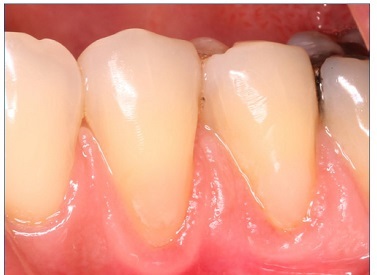

There were no dropouts in this study, so all patients were evaluated at baseline and at 6 months. Representative images of restorations are presented in Figures 1, 2, 3, 4, 5, and 6.

Figure 4 Photographs after 6 months of tooth 44’s restoration by the self‑etch technique and tooth 45’s restoration by the etch‑and‑rinse technique